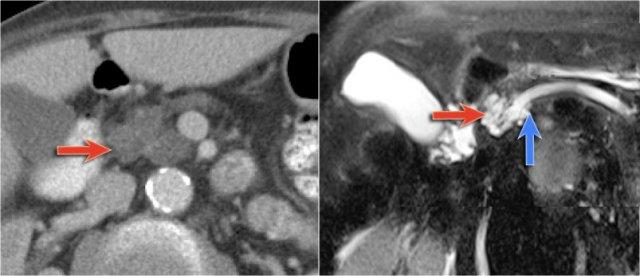

Hình ảnh CT của bệnh nhân nữ 30 tuổi có tiền sử viêm tụy do sỏi mật và đã cắt túi mật.

Bệnh nhân xuất hiện đau bụng trái đột ngột tăng nặng.

Siêu âm cho thấy tổn thương dạng nang tăng kích thước, được chẩn đoán là nang giả tụy (pseudocyst).

Tuy nhiên, CT cho thấy tổn thương dạng nang không có thùy hóa ở đuôi tụy với các vách ngăn bên trong có ngấm thuốc, không thông với ống tụy chính (hình).

Tiếp tục xem hình ảnh MRI…

Chuỗi xung T1W sau tiêm thuốc tương phản từ Gadolinium thể hiện rõ hơn các vách ngăn bên trong.

Phẫu thuật cắt đuôi tụy xác nhận u nang tuyến nhầy kích thước 14 cm có mô đệm buồng trứng (ovarian stroma).